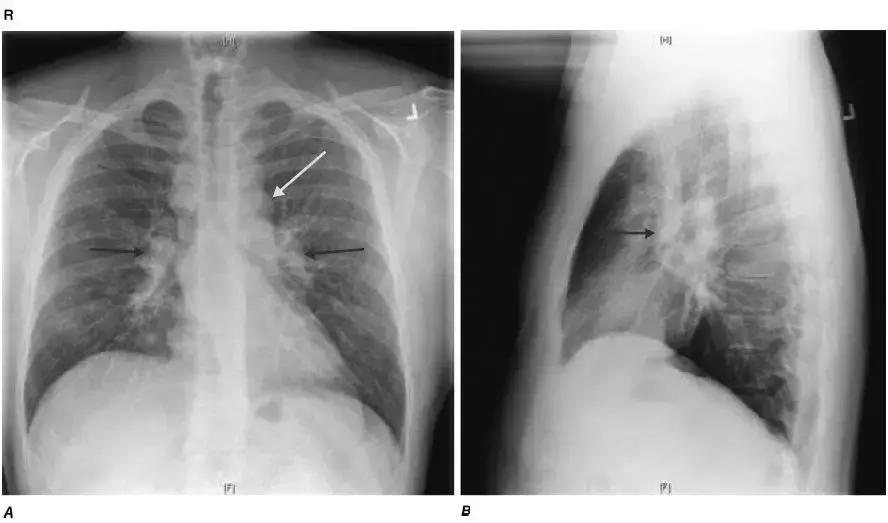

图4-21 A.正位胸片:气管旁(蓝箭头)、主肺动脉窗(黄箭头)和肺门淋巴结肿大(紫箭头);B.侧位胸片:肺门淋巴结肿大(紫箭头)